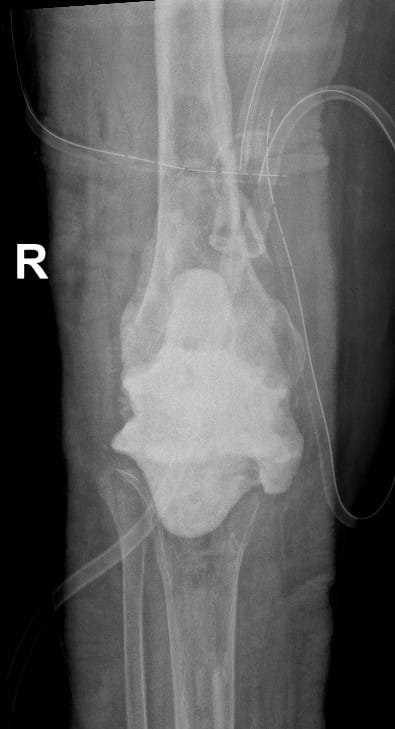

Although there has been an attempt to perform knee replacement in the 19th and early 20th century, Total Knee replacement surgery has come a long way since 1970s with continuous improvement in the design of implants and fixation techniques. Success from Charlney’s hip replacement surgery got surgeons and engineers interested again leading to modern-day implants. It has been successfully being performed worldwide from 1980 onwards. Diseased part of femur and tibia are removed using special instruments and metal implants mimicking design of femur and tibia are inserted using antibiotic-laden polymethyl methacrylate (bone cement). A polyethylene inset is fixed onto the tibial implant thus allowing movement at the knee joint. The undersurface of patella may be replaced with a patellar button in some cases. Due to improved technique and implant design, this surgery has gained immense popularity and has given a new lease of life for the patients suffering with arthritis of the knee joint. Patients can walk comfortably with the help of support following surgery and aren’t dependent on others for day-to-day life activities. Quality of postoperative care in recent times has further boosted the confidence among the patients undergoing this surgery. Patients are taught to strengthen the thigh muscle post-operatively and encouraged to become mobile. Gradually, they learn to climb stairs and later they walk around independently without any aided support. It is recommended that patients should not sit on the floor or squat. This helps maintain the longevity of the implants. As per the American Association of Orthopaedics, success rate of total knee replacement after 15 years is almost 90% and at the end of 25 years is almost 82%.

In total knee replacement surgery, we remove the damaged area over the femur, tibia and patella in the knee joint. It is replaced it with metal implants which are in the shape of these bones. These metal implants are fixed over your bone with the help of bone cement. Implants come in various sizes and you will get the best fit suited for you.